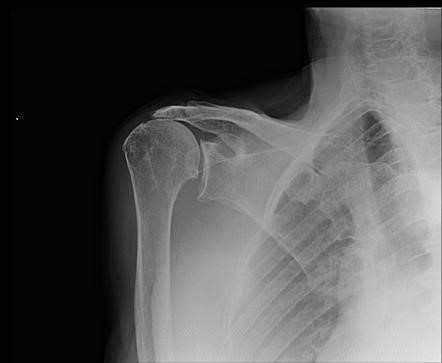

Bệnh lý chóp xoay dẫn tới thoái hóa khớp vai

Bệnh khớp chóp xoay là một dạng đặc biệt của bệnh thoái hóa khớp vai do rách chóp xoay dẫn đến mòn ổ chảo cánh tay bất thường và sau đó là sự di chuyển lên trên của chỏm xương cánh tay. Bệnh thường gặp ở phụ nữ trên 70 tuổi. Chẩn đoán có thể được thực hiện chủ yếu bằng chụp X-quang và Cộng hưởng từ thấy hình ảnh thoái hóa khớp. Để có phương án điều trị phù hợp đòi hỏi phải thăm khám kỹ lâm sàng và đánh giá hình ảnh phim chụp, điều trị thường phẫu thuật thay khớp vai để cải thiện triệu chứng lâm sàng và chức năng vận động khớp vai